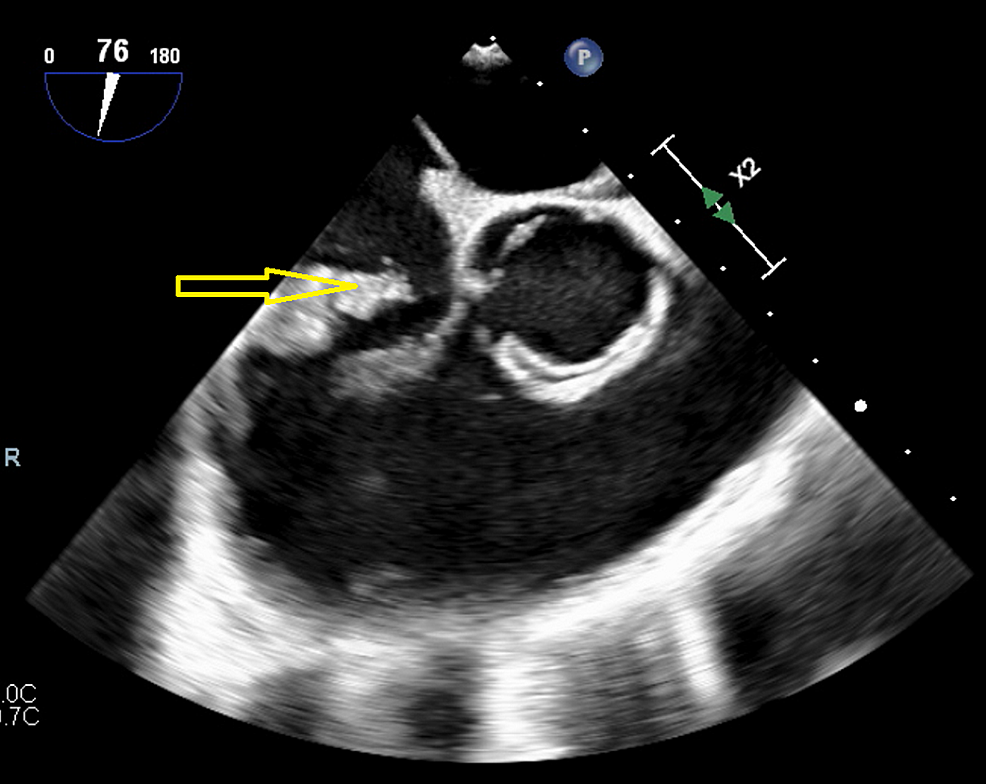

From www.semanticscholar.org

Figure 1 from Thrombolysis in the Obstructed Prosthetic Tricuspid Valve Importance Of Tricuspid Valve the tricuspid valve is complex anatomically, lying adjacent to important anatomic structures such as the right. the tricuspid valve forms the boundary between the right ventricle and the right atrium. Deoxygenated blood enters the right side of the heart. an appreciation of the complex and variable anatomy of the tricuspid valve is essential to unraveling the pathophysiology. Importance Of Tricuspid Valve.

From johnsonfrancis.org

Vegetation on tricuspid valve echocardiographic image All About Importance Of Tricuspid Valve the tricuspid valve forms the boundary between the right ventricle and the right atrium. the tricuspid valve is complex anatomically, lying adjacent to important anatomic structures such as the right coronary. Deoxygenated blood enters the right side of the heart. the tricuspid valve is complex anatomically, lying adjacent to important anatomic structures such as the right. . Importance Of Tricuspid Valve.